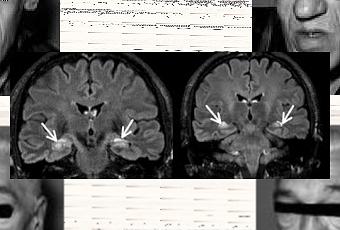

Encéphalite limbique: IRM pondérée en séquence Flair. Coupes coronales retrouvant des hypersignaux bitemporaux (flèches blanches). In La revue de médecine interne Volume 32, Issue 12, December 2011, Pages 742 - 750